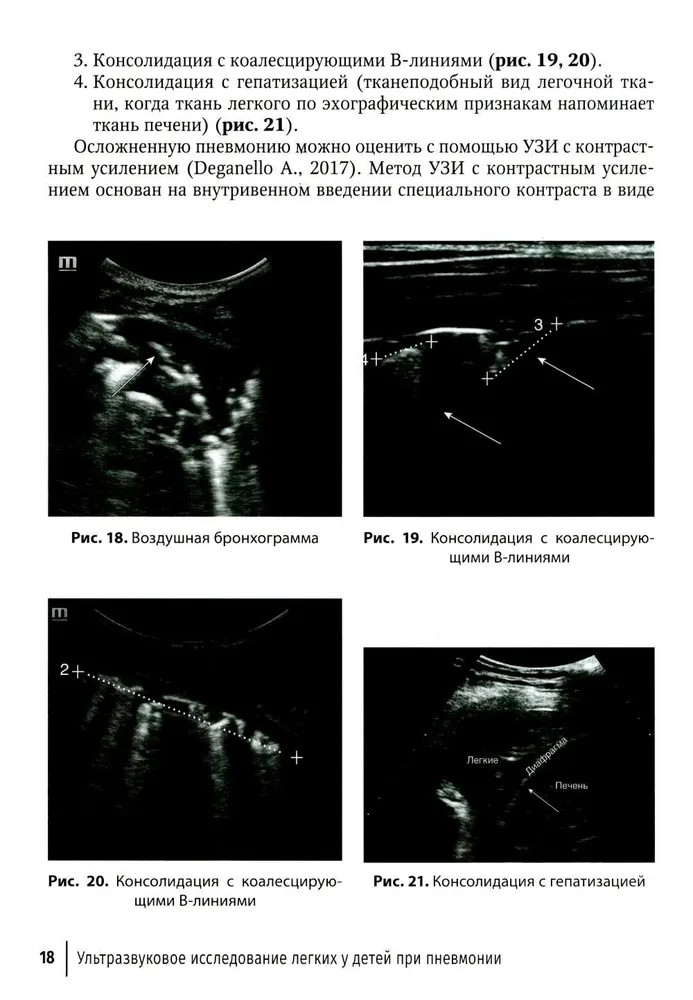

%text%